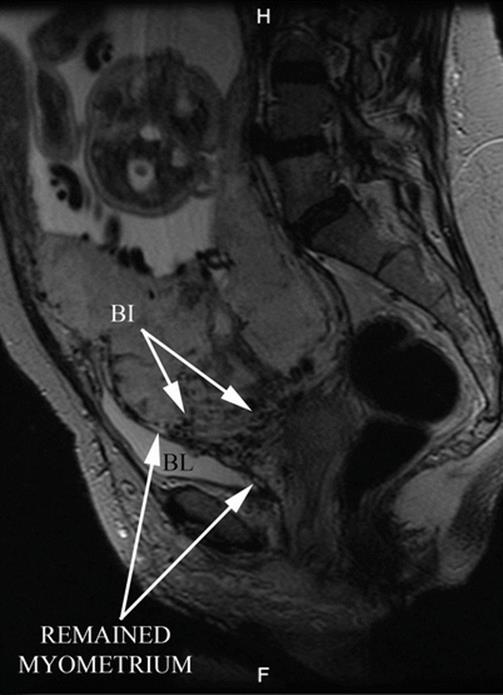

Identification of S1 and S2 areas can be established by pMRI, sagittal slice (Fig. 14.10). A line that perpendicularly crosses the middle of the posterior bladder wall determines an upper area named S1, which mainly corresponds to the uterine body, and an area below this line, named S2, which involves the lower segment, cervix and upper vagina [9]. Most part of AIP is located in S2 area, which also explained the high rate of failures with the use of uterine or internal iliac vascular control.

Fig. 14.10

Sagittal MRI T2 image: perpendicular plane which divide the posterior bladder wall determine an areas S1 and S2. White arrow shows an interrupted myometrium. Lagoons and vessels are clearly visible in the myometrial-bladder interphase